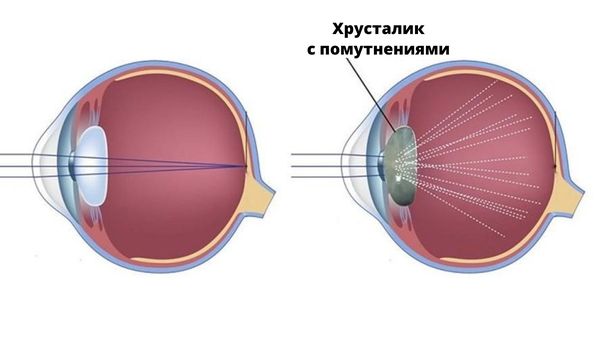

- катарактой (помутнением хрусталика);

То же самое происходит и при катаракте: из-за помутнения хрусталика глаз получает недостаточное количество света для чёткого изображения и видит будто через грязное стекло, что вызывает ощущение двоения. Иногда монокулярная диплопия возникает уже после лечения катаракты, если искусственный хрусталик смещается и начинает неправильно преломлять световые лучи.

Помутневший хрусталик

У пожилых пациентов двоение чаще всего связано с катарактой, поэтому им обычно удаляют помутневший хрусталик или заново фиксируют искусственный хрусталик.